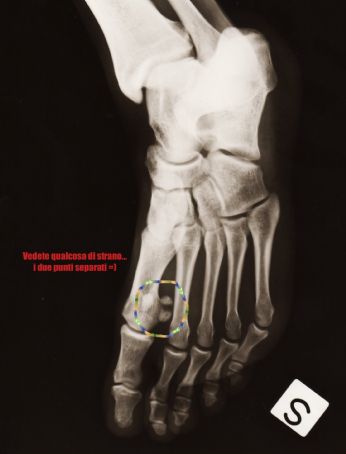

Il Mio Piede

LEGGI I COMMENTI (3) - PERMALINK